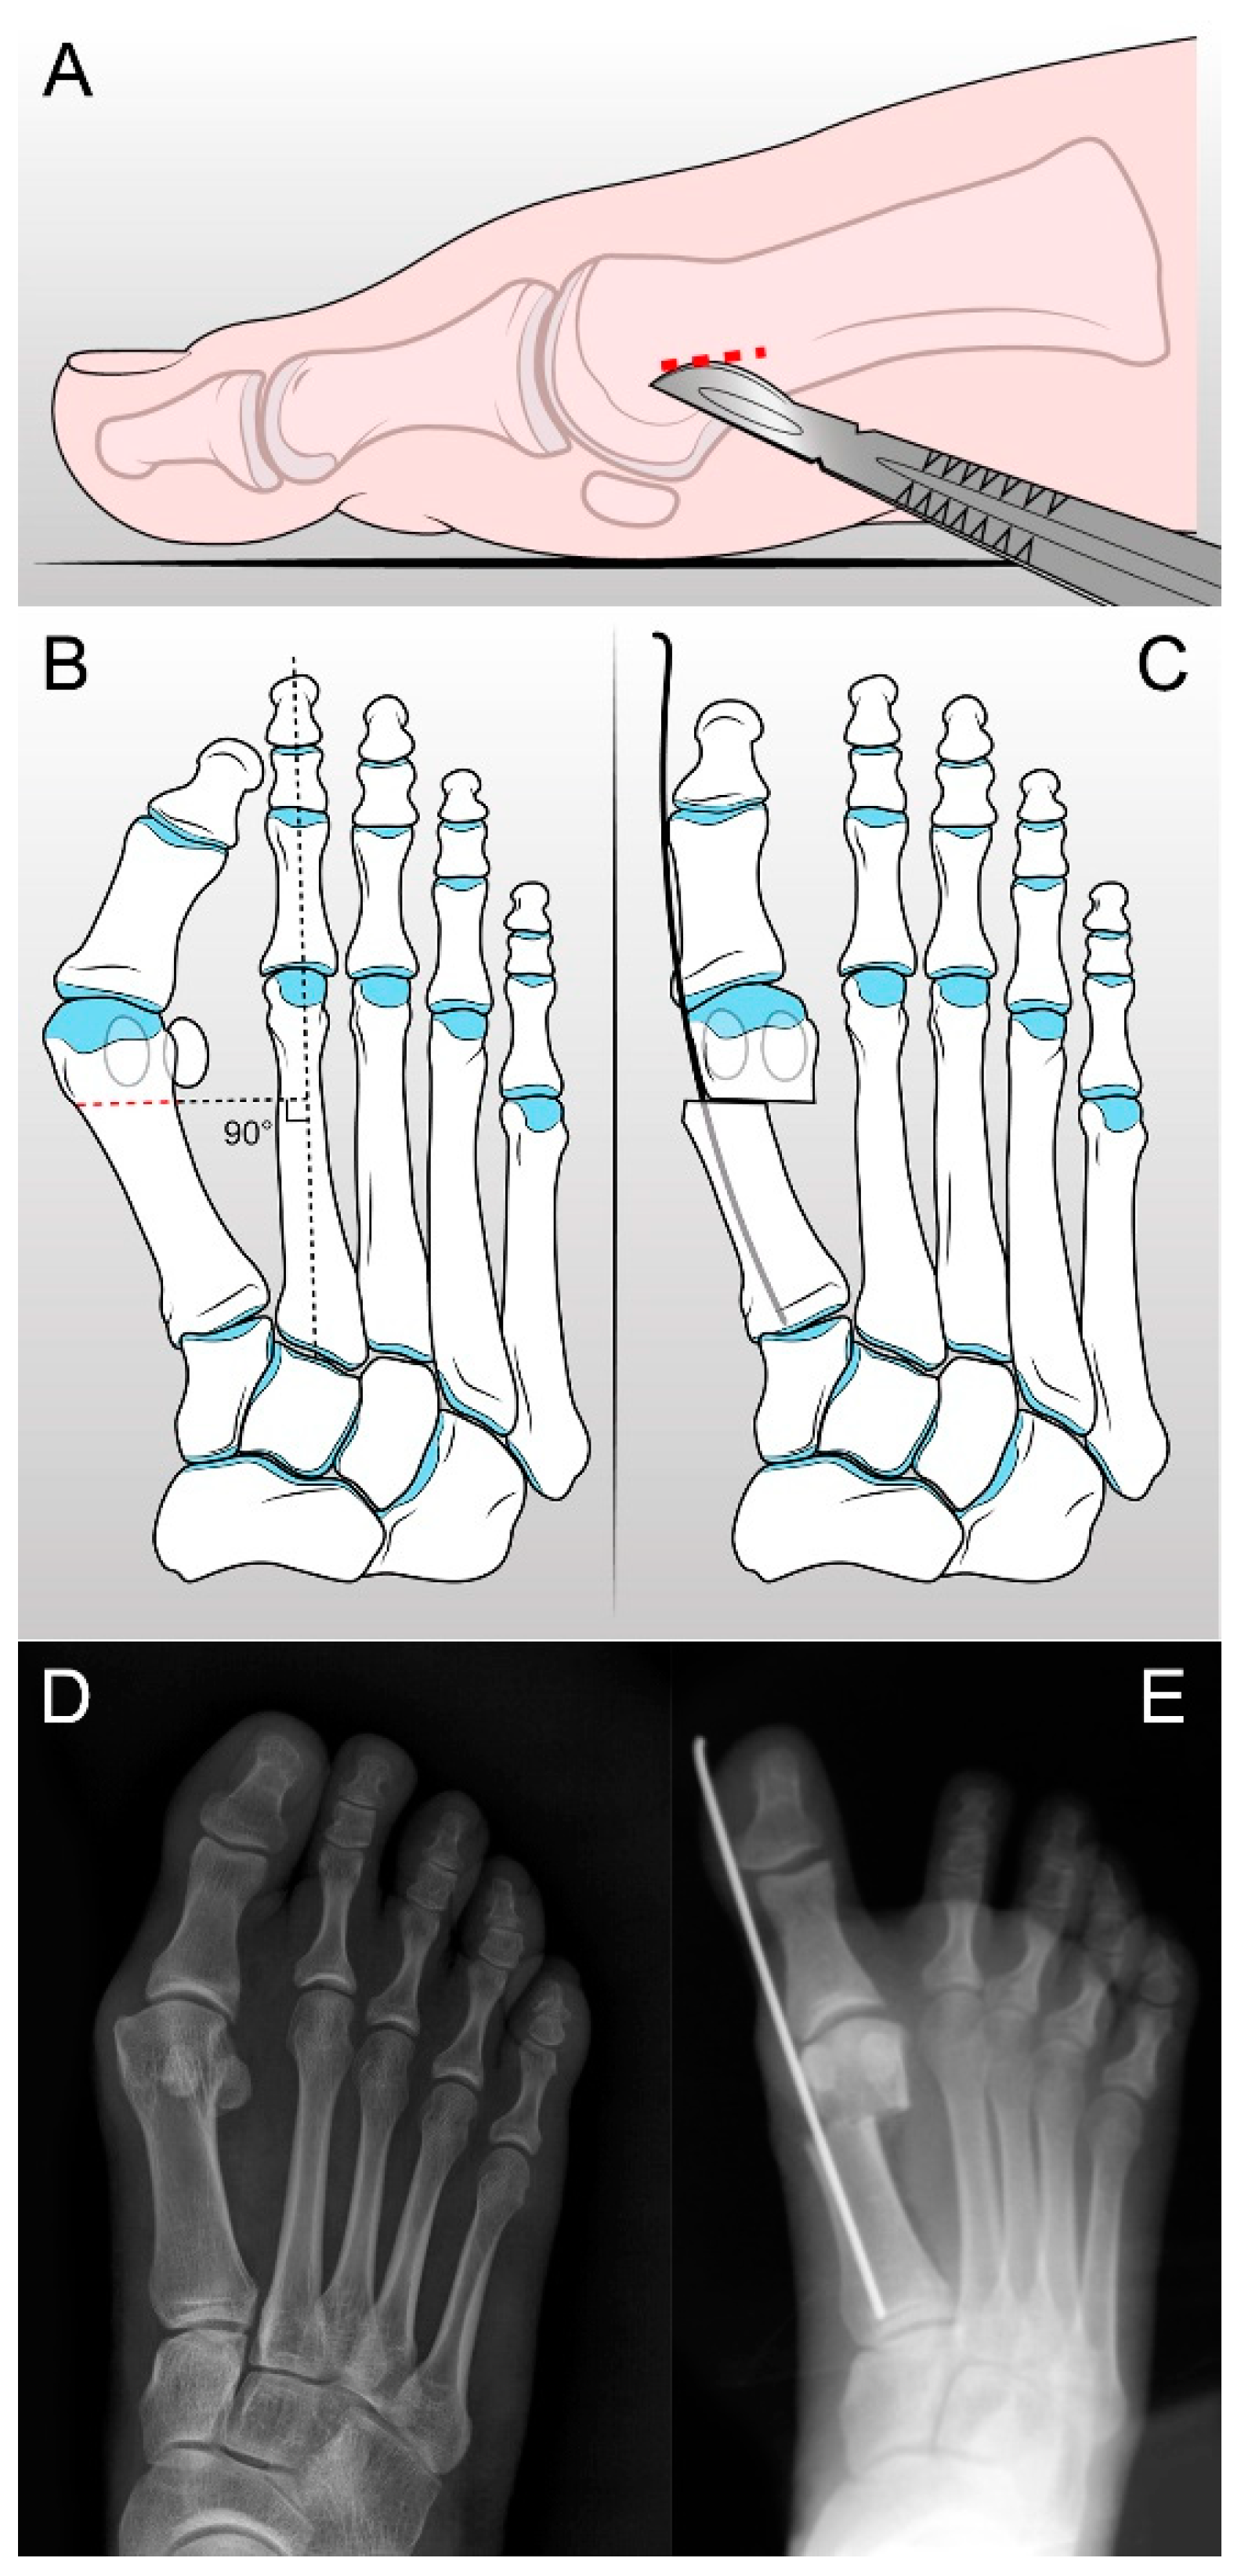

2.2. S.E.R.I. Operative Technique and Postoperative Management

- Giannini, S.; Faldini, C.; Nanni, M.; Di Martino, A.; Luciani, D.; Vannini, F. A minimally invasive technique for surgical treatment of hallux valgus: Simple, effective, rapid, inexpensive (SERI). Int. Orthop. 2013, 37, 1805–1813. [Google Scholar] [CrossRef] [PubMed]

- Giannini, S.; Faldini, C.; Vannini, F.; Digennaro, V.; Bevoni, R.; Luciani, D. The minimally invasive osteotomy “S.E.R.I.” (simple, effective, rapid, inexpensive) for correction of bunionette deformity. Foot Ankle Int. 2008, 29, 282–286. [Google Scholar] [CrossRef] [PubMed]

- Giannini, S.; Cavallo, M.; Faldini, C.; Luciani, D.; Vannini, F. The SERI distal metatarsal osteotomy and Scarf osteotomy provide similar correction of hallux valgus. Clin. Orthop. Relat. Res. 2013, 471, 2305–2311. [Google Scholar] [CrossRef] [PubMed]

- Rocca, G.; De Venuto, A.; Mazzotti, A.; Zielli, S.O.; Artioli, E.; Brognara, L.; Traina, F.; Faldini, C. The Minimally Invasive SERI Osteotomy for Pediatric Hallux Valgus. Children 2023, 10, 94. [Google Scholar] [CrossRef]

- Almalki, T.; Alatassi, R.; Alajlan, A.; Alghamdi, K.; Abdulaal, A. Assessment of the efficacy of SERI osteotomy for hallux valgus correction. J. Orthop. Surg. Res. 2019, 14, 28. [Google Scholar] [CrossRef]